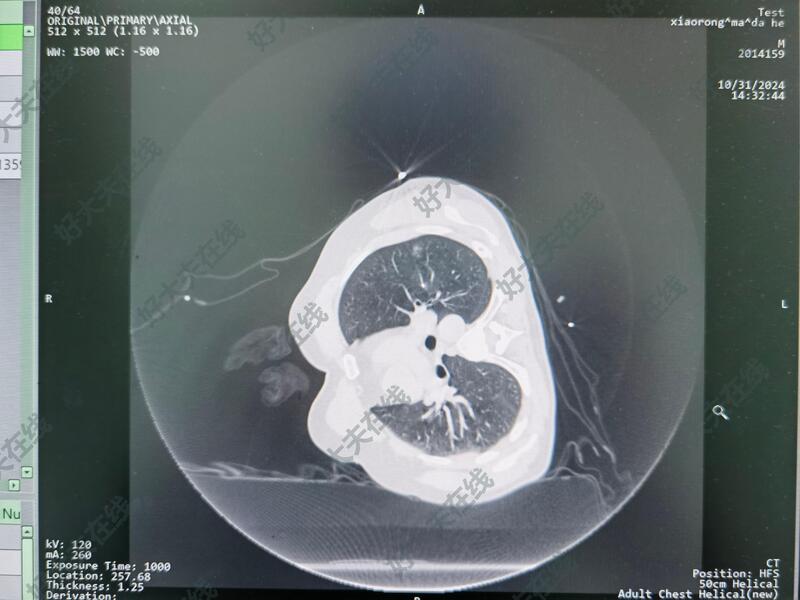

治疗中

采取CT引导,消融针精确肿瘤位置,60w,4分钟,消融边界清晰,治疗效果满意。